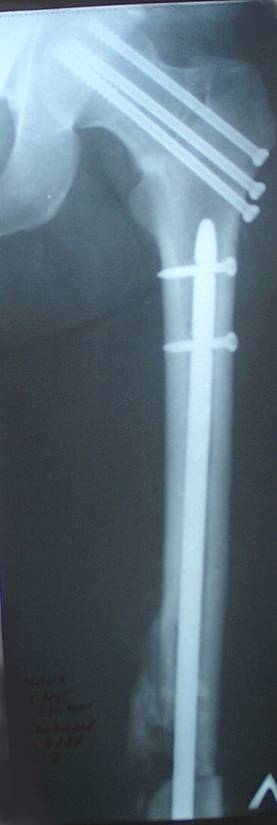

Уважаемый Сергей, избрав вариант DHS плюс ретроградный гвоздь Вы явно обезопасите себя от проблем, связанных с введением штифта через trochanteric fossa. Очень это может быть проблематично, Вы правы. Поэтому DHS плюс ретроградный гвоздь - спокойно выполнимый вариант, особенно в "чужом" отделении. Схожий свой случай из далёкого теперь уже 1999г. прилагаю, только вместо канюлированных винтов у Вас будет DHS (VHS). А если антеградный гвоздь - то только из тех, что предназначены к введению через верхушку вертела. И это тоже выполнимо, но сложнее. Мне так кажется.

Уважаемый Сергей Витальевич! Мы в похожем случае выбрали вариант DHS + DFN. Правда из 4 кортикальных винтов накладки DHS - 2 пришлось вводить монокортикально - уперлись в штифт.. На конечный результат это не повлияло. Ссылка здесь.

Буду бить DFN плюс DHS